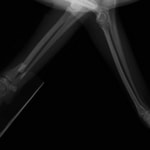

症例3:キルシュナーワイヤーのピンニングによる整復

ペルシャ猫 11ヶ月齢 雄

他院にて左大腿骨遠位の成長板骨折(salter-harrisⅠ型)が認められており、治療相談を目的として来院。当院にて、キルシュナーワイヤーを用いたピンニングにより骨折部位の整復を行いました。術後の経過は良好で、現在も経過観察中です。

術前レントゲン

術後レントゲン

機器

Arthrex社のターゲティングデバイスを用いてピンニングの位置を調整することで、確実な固定を行っています。当院ではこの手術器具以外にも、人の手術にも使用される様々な器具を導入し、手術精度を高め、また医療メーカーと新しい器具の開発、試作にも取り組んでおります。